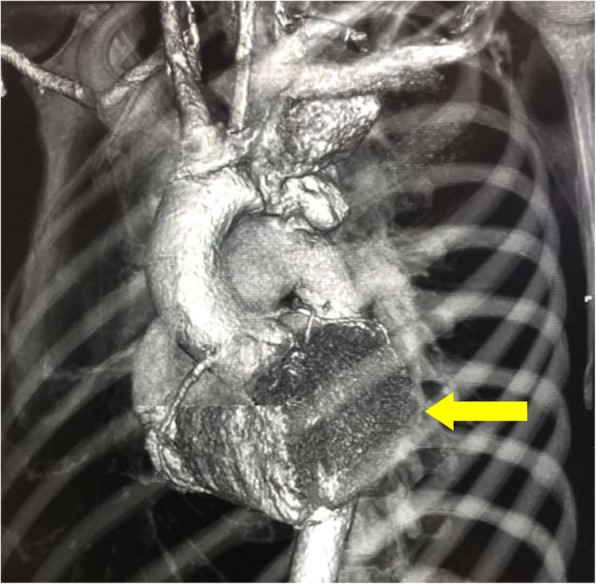

Fig. 2.

A reconstructed CTA showing the position and relative size of the aneurysm in the descending aorta (yellow arrow) near left subclavian artery

A 30 year-old female patient presented with left sided chest pain and intermittent fever and cough for 6 months and massive hemoptysis for a week. There was a history of cerebral venous sinus thrombosis in the sigmoid sinus about 2 years ago for which she received Rivaroxaban. Chest X-ray revealed widened mediastinum (Fig. 1). Upon investigating through CT scan, pseudo-aneurysm of proximal descending thoracic aorta at the level of the left Subclavian artery was found (Fig. 2); the diameter was 83 mm, with a patent lumen of 33 mm. A partially occluding thrombus was also present, as seen in Fig. 3. Consequently the patient was admitted and Internal Medicine team was consulted preoperatively to rule out mycotic aneurysm. Serology including AMA, ANA, VDRL, IgG and IgM were all negative; however an ESR of 90 was obtained.